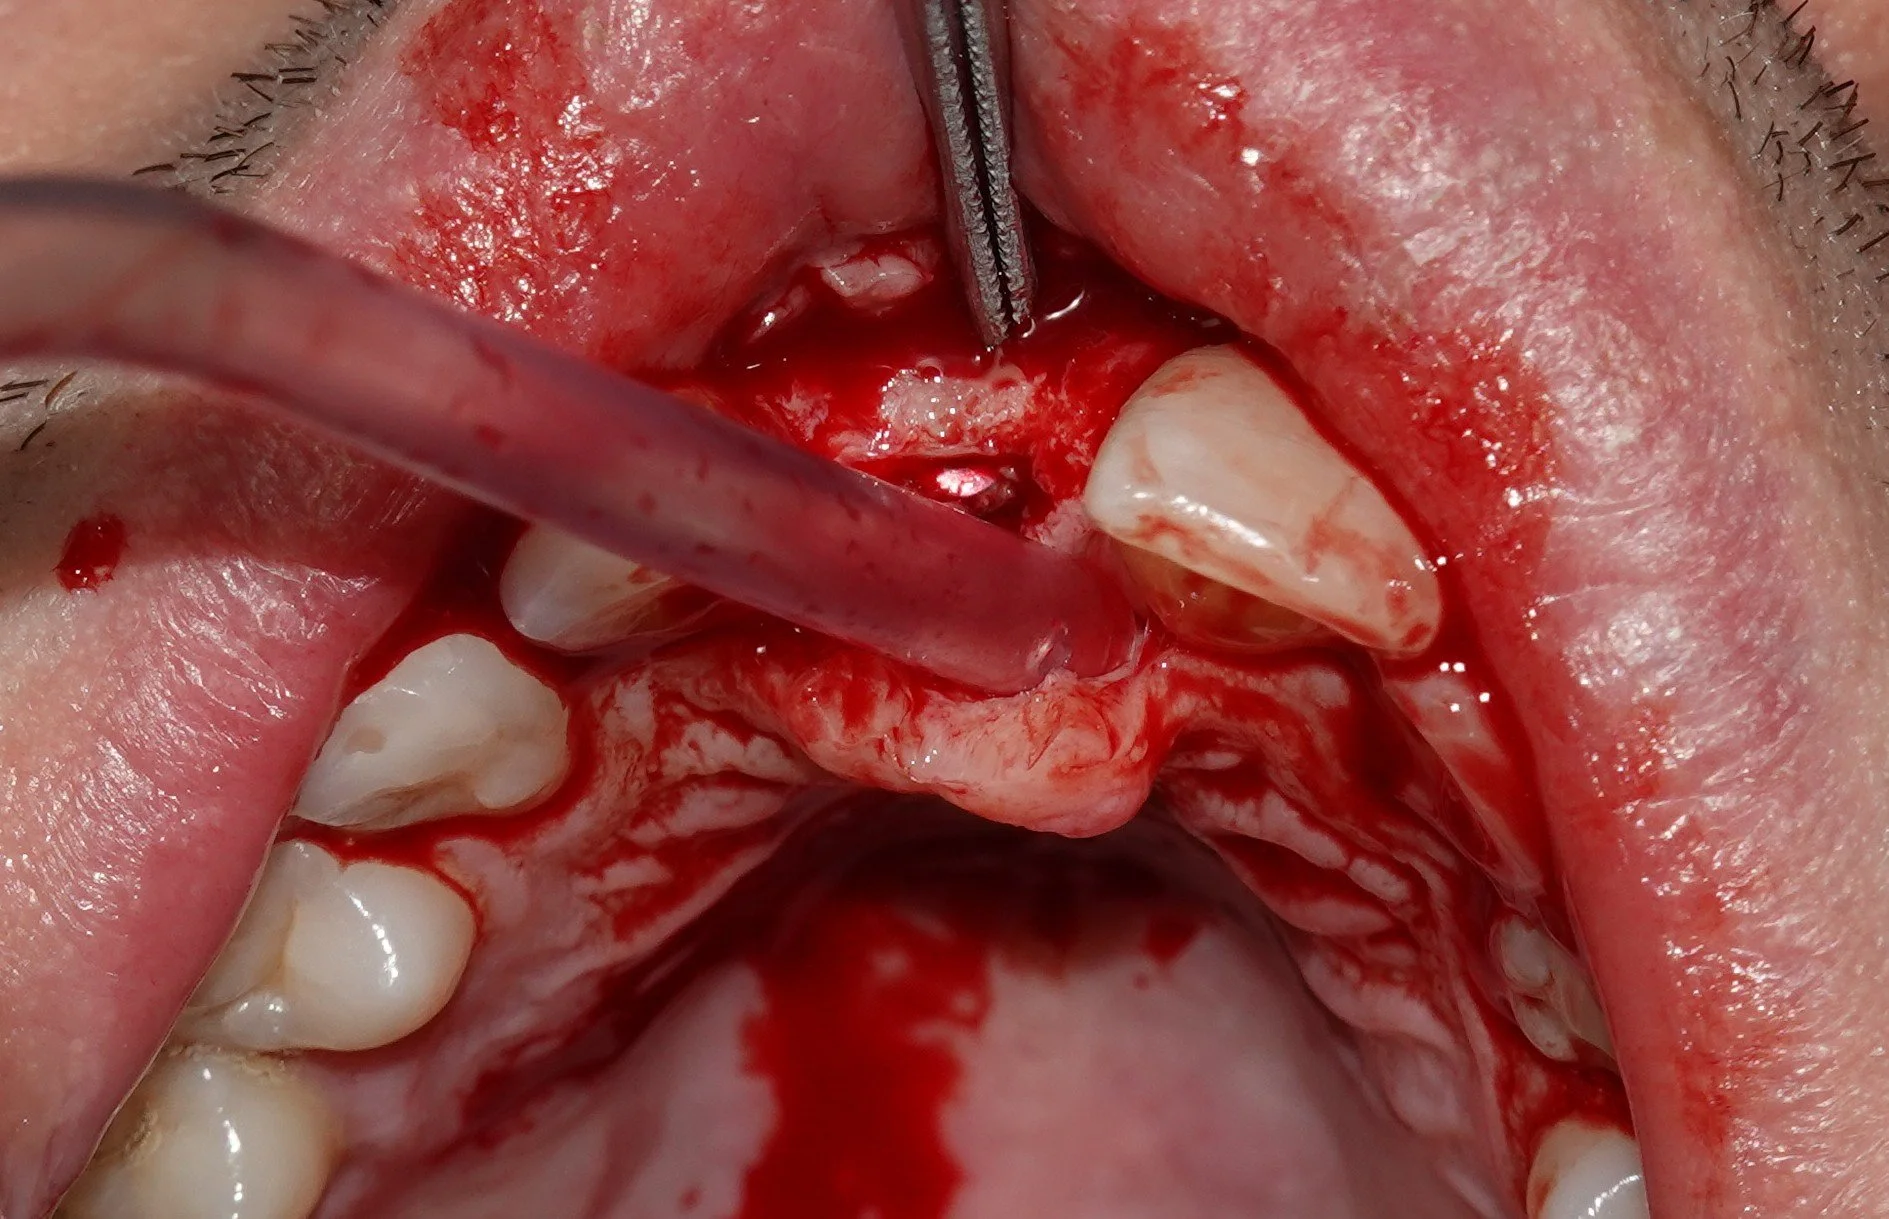

Our training programs blend flexible online learning with immersive hands-on workshops, equipping dentists with knowledge, confidence, and skills to deliver predictable, high-quality implant treatments.

This channel is for dentists interested in learning disciplines related to dental and extra-oral implants. It covers basic sciences, fundamentals of oral surgery, prosthodontic principles, diagnostic and treatment planning foundations, and sciences associated with dental implants.

Over his academic and professional career, Dr. Nik has placed more than 10,000 dental implants, ranging from routine cases to complex surgical and prosthetic treatments. He has extensive experience managing challenging cases involving bone grafts, nerve repositioning, sinus augmentations, and extra-oral implants, treating patients aged 12 to 90, including those with systemic conditions such as oligodontia and scleroderma.